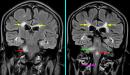

- التصلب المتعدد: (بالإنجليزية: Multiple sclerosis) والمعروف أيضاً بالتصلّب اللويحي الذي يحدث نتيجة مهاجمة الجهاز المناعي لغمد الحماية المسمى بالميالين (بالإنجليزية: Myelin sheath) الذي يغطي الألياف العصبية، فيؤدي إلى حدوث خللٍ في الاتصال بين الدماغ وبقية الجسم، وقد يتسبّب بتدهور وظيفة الأعصاب أو التلف الدائم لها في نهاية الأمر.[١١]

- السكتة الدماغية: تحدث السكتة الدماغية بسبب انقطاع إمدادات الدم إلى جزء من الدماغ أو تناقصها بشدة، مما يحرم أنسجة المخ من الأكسجين والمواد المغذية، فتبدأ خلايا الدماغ بالموت في غضون دقائق.[١٧]